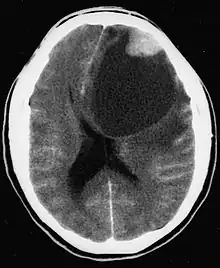

| CT scan of a brain with pleomorphic xanthoastrocytoma. The classic radiographic appearance is one of a superficially situated tumor, here a mural nodule, associated with an underlying cyst. |

Pleomorphic xanthoastrocytoma usually develops within the supratentorial region (the area of the brain located above the tentorium cerebelli). It is generally located superficially (in the uppermost sections) in the cerebral hemispheres and involves the leptomeninges. It rarely arises from the spinal cord.

These tumors are formed through the mitosis of astrocytes. They are found in the area of the temples, in the brain's frontal lobe or on top of the parietal lobe. In about 20% of cases, tumors exist in more than one lobe.